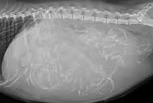

Appareil de radiologie

Des examens d’imagerie précis et rapides

Notre cabinet est équipé d’un appareil de radiologie numérique moderne, offrant des images de haute qualité en quelques secondes.

Cet équipement permet un diagnostic fiable des affections osseuses, thoraciques ou abdominales.

Les clichés sont interprétés directement au cabinet pour une prise en charge rapide et efficace de votre animal.